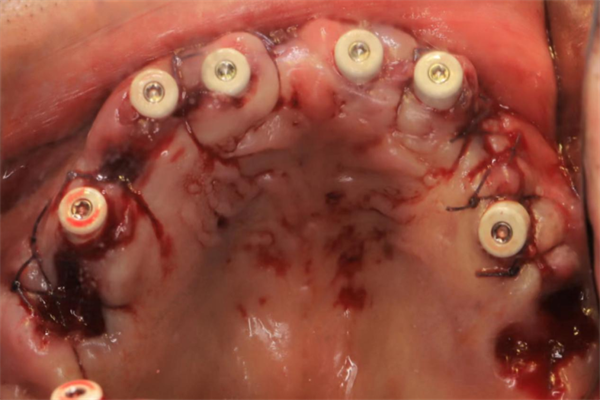

使用數(shù)字化3D打印導板定位

術前,楊濤主任與王可醫(yī)生對李伯擬種植區(qū)牙體、牙周狀況、牙槽骨、咬合關系、全身健康狀況等進行了精細的檢查與評估,并定制了數(shù)字化導板。

手術當天,楊濤主任帶領團隊在麻醉科的協(xié)助下,整個拔牙及種植過程十分順利。術后X線片顯示,種植體的植入深度、角度,高度都非常精準。